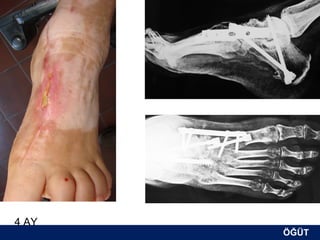

OLGU No 4

FK, 51y, K

10 yıldır oralad

4 AY

ÖĞÜT